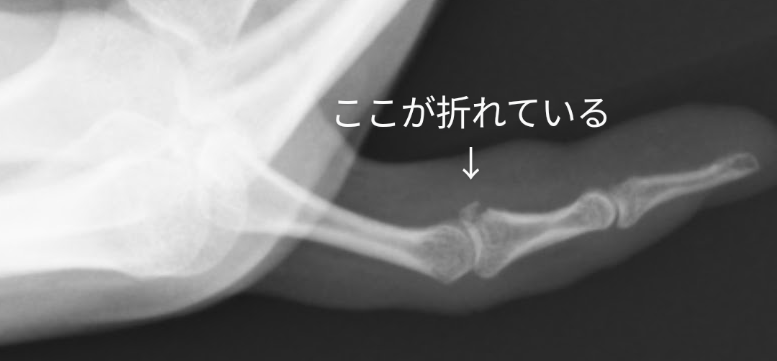

右手第5指損傷

X-P画像